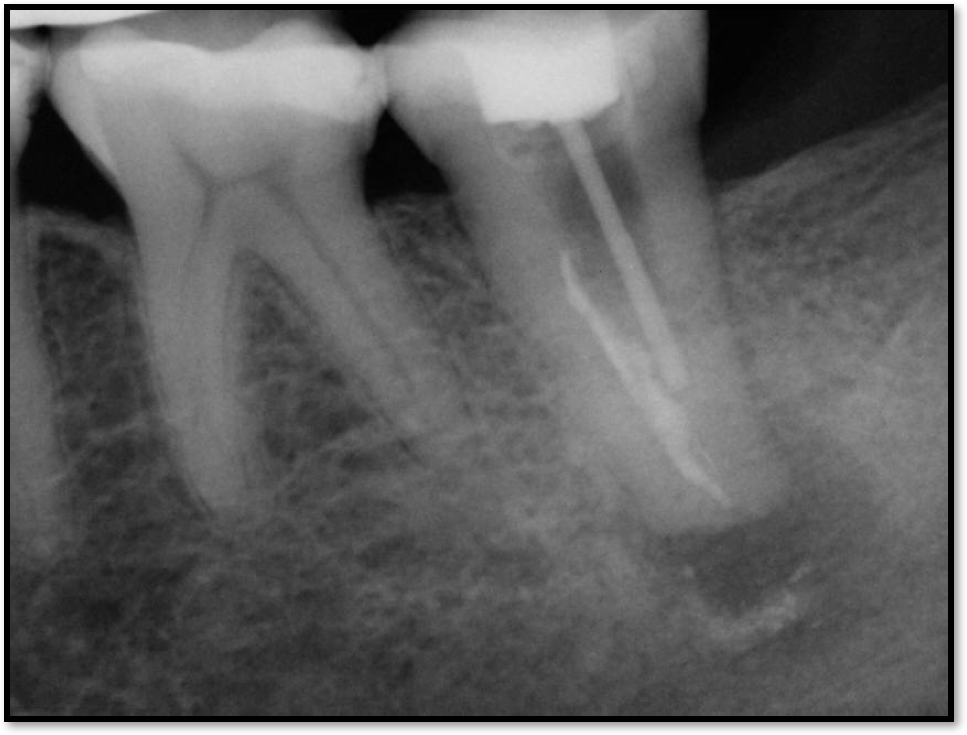

Occlusion is one of the most overlooked areas in endodontics; however, other than remaining structure, it is the most important factor.7 Patients who are heavy bruxers can cause the need for a root canal from the lateral forces. Patients who clench pose a different challenge with apical forces, yet the damage from both can be the same. Figure 7 shows a patient with bruxism. The patient had pain in response to hot and cold stimulus, and the clinicians needed a bitewing to determine which tooth was causing the pain. From the periapical (PA), it was clear that tooth No. 2 had a large problem, No. 3 had a crown, and No. 4 had a large restoration. Any of the three may have been the source of the problem.

With the bitewing shown in Figure 8, it became clear there was gross decay in tooth No. 3 that could not be seen on the PA, and there was a periodontal defect, a pulp stone, in No. 2. There was also a class V lesion revealing the bruxism, flat occlusion, multiple restorations in No. 30, a post in No. 31, and decay on No. 2 as well. The post in No. 31 was useless because when a post is placed, it must be the right length, width, and size. If the post is too short, there will be a greater fulcrum and the tooth will break. If it is too long, the clinician can break it by wedging it. If it is too short, it will not hurt the tooth, but it will not provide any valuable function. It is overall preferable to do posts in teeth having just single restorations rather than abutments for bridges because those teeth are already under greater force. If the technique is not performed correctly, iatrogenic issues may result.

Fig 8. Bitewing revealed decay and other problems.

Figure 8